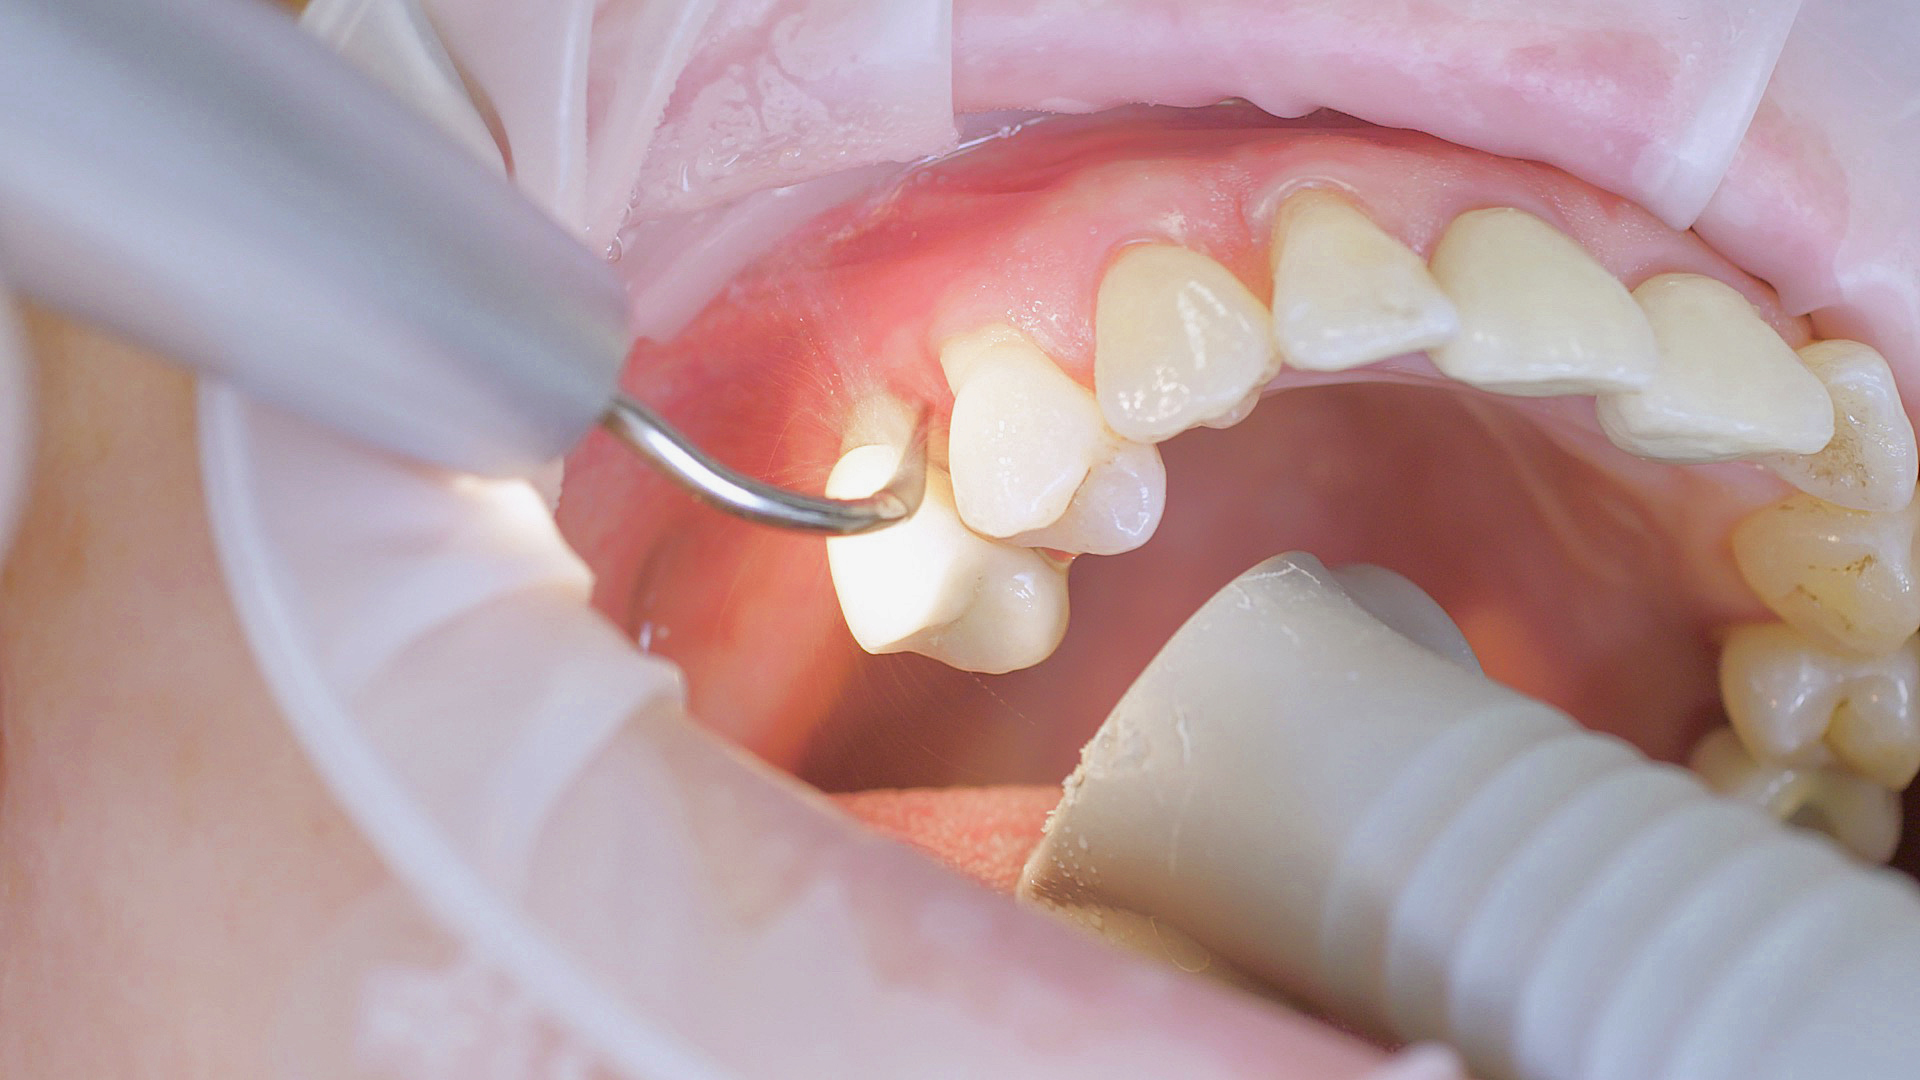

Where necessary, initial periodontal treatment is carried out. First, professional tooth cleaning establishes healthy gingival conditions. In this procedure, calculus (Fig. 1) and biofilm (Fig. 2) are removed as far as the gingival sulcus. In combination with careful instruction on oral hygiene, this gives the patient the basis for long-term freedom from inflammation.15

Removal of subgingival coatings (debridement) is carried out using sonic or ultrasonic devices and special periodontal tips as initial periodontal treatment (Fig. 3). Manual instruments can also be used. Further surgical and/or regenerative measures may be necessary, depending on the situation.